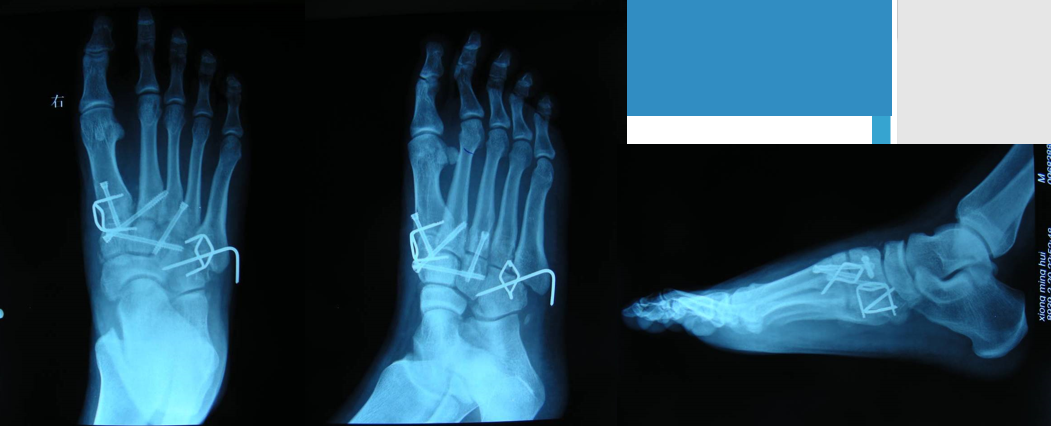

在足正位X线上,第1、2、3跖骨的内外侧缘分别和它相对应的楔骨的内外侧缘呈一直线排列;第一、二跖骨基底间隙和内中楔骨间隙相等。

30°斜位上:1、第四跖骨内侧缘和骰骨内侧缘连续成一条直线2、第三跖骨内侧缘和外侧楔骨内侧缘连续成一条直线3、第二、三跖骨基底间隙和内、中楔骨间隙相等。

侧位上,跖骨不超过相应楔骨背侧缘。从远端的跖骨经过跖跗关节到近端的跗骨,应该是一条不间断的连线

2005年Pearse等提出“ABC”的方法来阅读足部X 线片, 以减少中、前足的漏诊。 A ( alignment)检查跖骨与相应楔骨的对应线 B ( bone)检查每一块骨的轮廓 C ( congruity )检查整体一致吻合, 在正位片上观察内柱, 在斜位片上观察中、外柱。侧位片的常规检查可发现Lisfranc关节矢状面的半脱位及撕脱性骨折

Lisfranc损伤骨折复位标准:1、C形臂透视显示正、侧、斜位均为正常解剖复位2、如复位后第1、2跖骨基底间隙和内、中楔骨间隙<2mm,跖跗骨轴线<15°为近解剖复位,可以接受,超过这个范围的移位则无法接受3、复位好后,沿第一跖骨轴线向内侧楔骨逆行拧入一枚4.0mm皮质骨螺钉。螺钉由关节远侧1.5-2.0cm处进入,平行于足底或略向跖侧。

术后管理石膏固定4~6周;如果固定稳定,术后两周可开始功能锻炼,4~6周部分负重,六周后完全负重;术后6~8周可拔去克氏针,术后3~4月可取出螺钉。有些人主张若无症状出现,可无限期地留置螺钉于体内